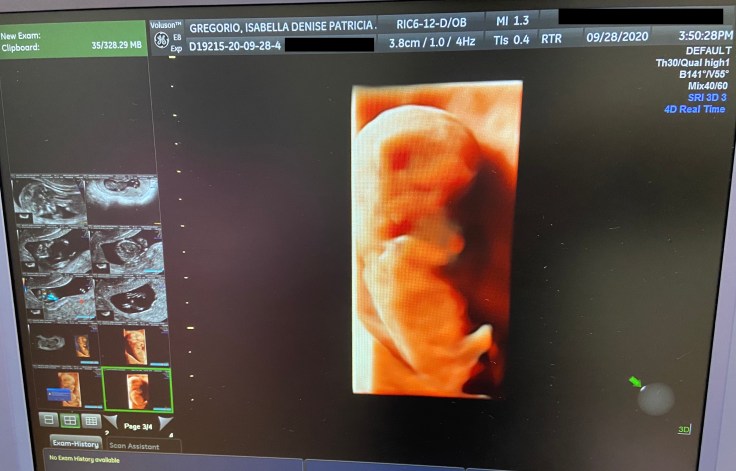

Scheduling for a blood extraction was nothing new; I had tons of experience in that department. Scheduling for a prenatal ultrasound however, that was uncharted territory. Waiting for the ultrasound felt like being next in line at a big audition (think Miss Saigon) except multiplied a thousandfold. With my heart beating out of my chest, clammy hands clasped in prayer, and a husband doing his best to look unfazed, I walked into the room with full surrender.

Seeing the baby for the first time and the flicker of its heartbeat felt like I had finally done something right in my life.